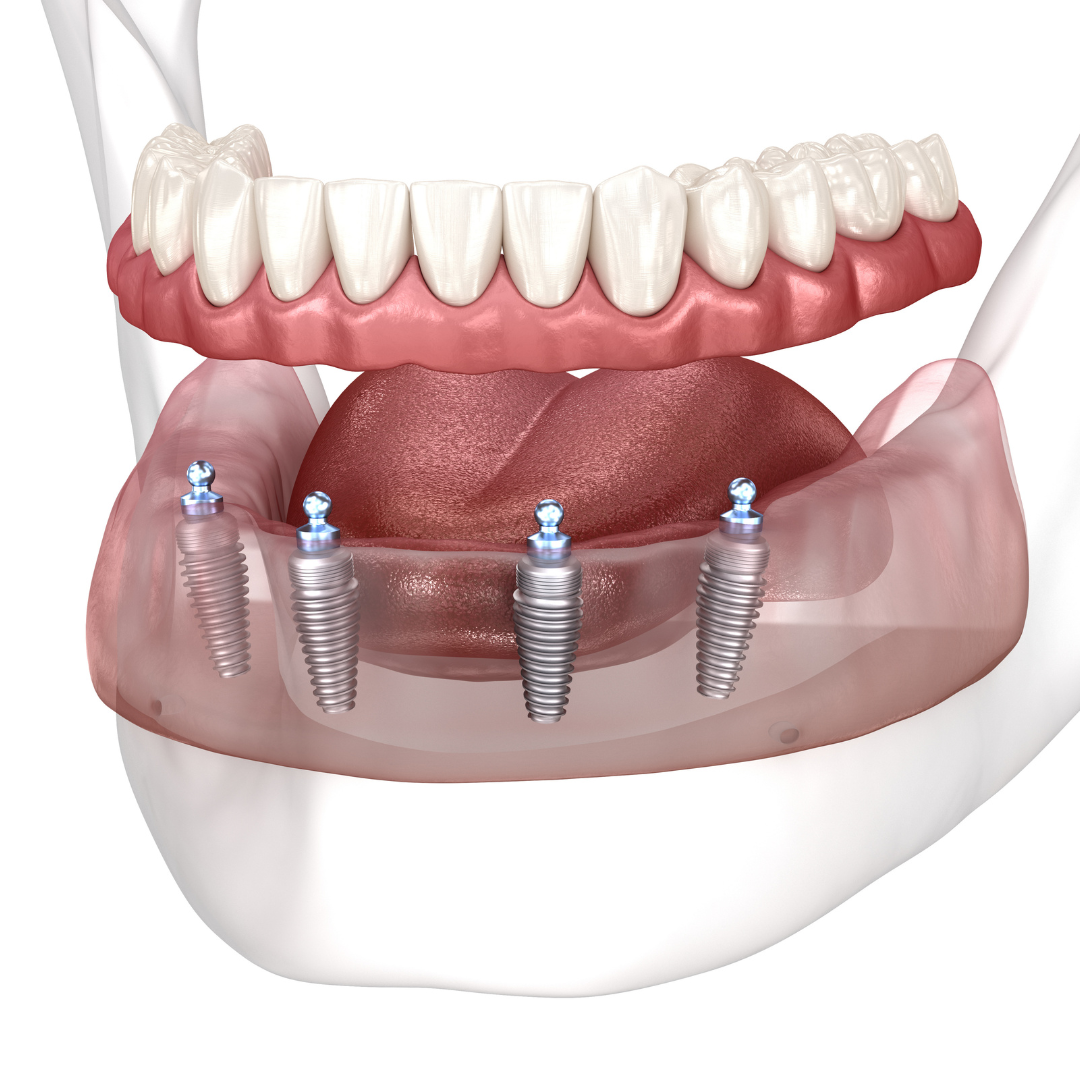

What are dental implants?

Learn how millions of Americans are replacing their teeth for life!

Patients no longer have to deal with low-quality temporary solutions like dentures, bridges, or partials. Dental implants are the new leading standard in tooth replacement options. They act and feel just like real teeth with an average lifespan of 20+ years.

So, how do they work?

Every single dental implant consists of three parts - the implant, the abutment, & the crown. The implant is made of medical grade titanium. This part is surgically placed into the patient’s jaw bone and left to heal for 4-6 months afterwards.

This implant piece acts as the foundation for the rest of the tooth. Once the bone around the site has healed, the abutment and crown are placed on top of the implant. The end result is a beautiful, natural-looking new tooth!

Few people will ever be able to tell the difference between your implants and your real teeth.